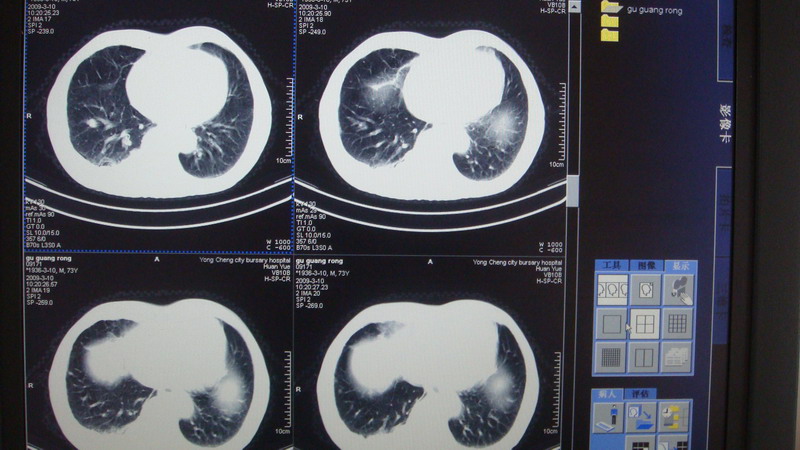

以下是引用光影相伴在2009-3-11 17:27:00的发言:[br]支持 右肺下叶周围型肺癌伴右肺门纵隔淋巴结转移;右上肺继发型肺结核(硬结\\纤维灶);右侧少量胸胸腔积液。另:不排除右侧胸膜转移可能。

以下是引用随光逐影在2009-3-11 16:57:00的发言:[br]支持 右肺下叶周围型肺癌伴右肺门纵隔淋巴结转移;右上肺继发型肺结核(硬结\\纤维灶);右侧少量胸胸腔积液。另:不排除右侧胸膜转移可能。

以下是引用草之原在2009-3-11 19:03:00的发言:[br]支持 右肺下叶周围型肺癌伴右肺门纵隔淋巴结转移;右上肺继发型肺结核(硬结\\纤维灶);右侧少量胸胸腔积液。另:不排除右侧胸膜转移可能。